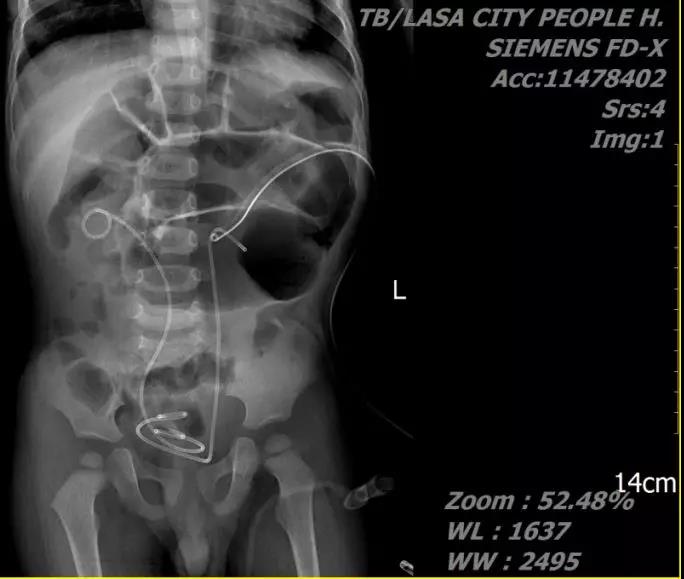

患儿,女,5岁,主因“右侧腰部疼痛1天”就诊,术前诊断:1.右输尿管结石,2.右肾结石。入院后决定一期行输尿管支架植入术,二期行mPCNL

术后患儿愈合良好,术后第3天拔除肾造瘘管,第4天拔出尿管,第5天出院。